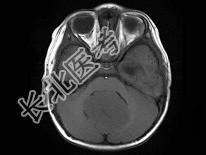

- 单项选择题男,2岁, 头痛、呕吐10余天,MRI检查如图所示, 最可能的诊断为 ( )

A、小脑蚓部髓母细胞瘤

B、星形细胞瘤

C、室管膜瘤

D、生殖细胞瘤

E、未见异常